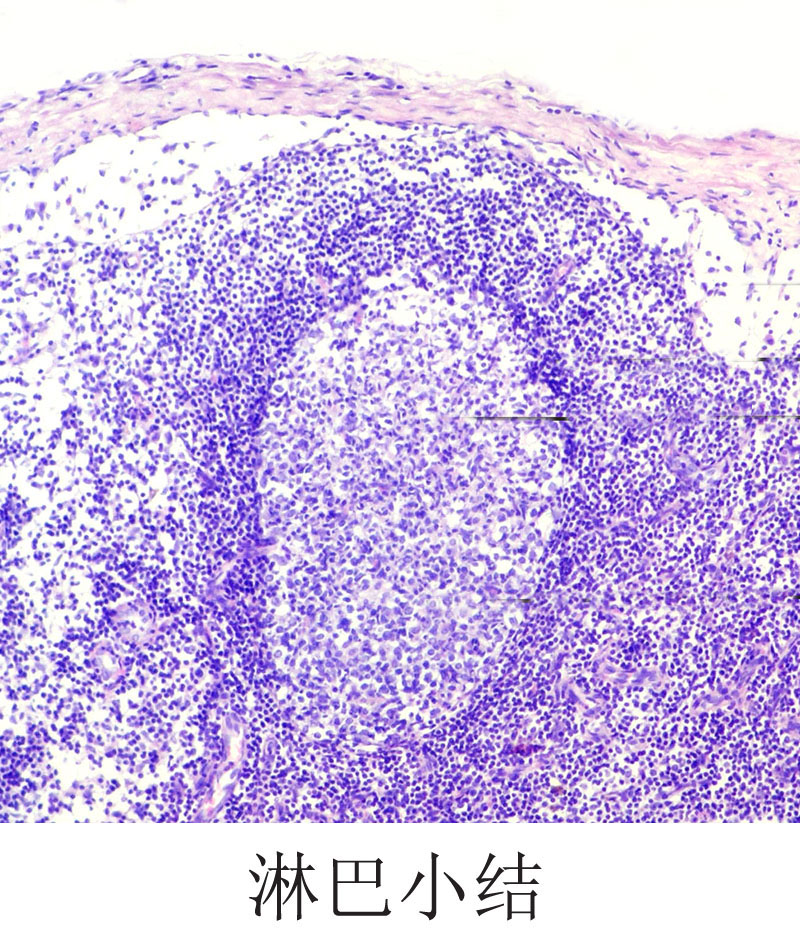

淋巴结活检镜下如图所示,应考虑何种疾病 ( ) -病理学高级职称题库总题库

淋巴小结,淋巴结手绘图,淋巴小结红蓝铅笔绘图(第3页)_大山谷图库